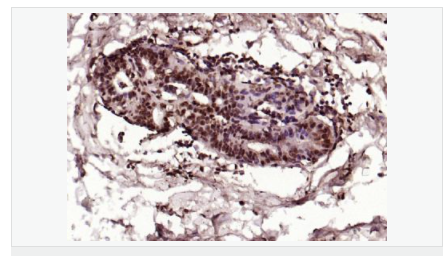

| 英文名稱(chēng) | phospho-HSP70 (Tyr611) |

| 中文名稱(chēng) | 磷酸化熱休克蛋白-70抗體 |

| 交叉反應 | Human, Mouse, Rat, (predicted: Dog, Pig, Rabbit, Guinea Pig, ) |

| 產(chǎn)品應用 | ELISA=1:5000-10000 IHC-P=1:100-500 IHC-F=1:100-500 Flow-Cyt=1μg/Test ICC=1:100 IF=1:100-500 (石蠟切片需做抗原修復) not yet tested in other applications. optimal dilutions/concentrations should be determined by the end user. |

| 產(chǎn)品介紹 | This intronless gene encodes a 70kDa heat shock protein which is a member of the heat shock protein 70 family. In conjuction with other heat shock proteins, this protein stabilizes existing proteins against aggregation and mediates the folding of newly translated proteins in the cytosol and in organelles. It is also involved in the ubiquitin-proteasome pathway through interaction with the AU-rich element RNA-binding protein 1. The gene is located in the major histocompatibility complex class III region, in a cluster with two closely related genes which encode similar proteins. [provided by RefSeq, Jul 2008]. Function: In cooperation with other chaperones, Hsp70s stabilize preexistent proteins against aggregation and mediate the folding of newly translated polypeptides in the cytosol as well as within organelles. These chaperones participate in all these processes through their ability to recognize nonnative conformations of other proteins. They bind extended peptide segments with a net hydrophobic character exposed by polypeptides during translation and membrane translocation, or following stress-induced damage. In case of rotavirus A infection, serves as a post-attachment receptor for the virus to facilitate entry into the cell. Subunit: Component of the CatSper complex. Identified in a mRNP granule complex, at least composed of ACTB, ACTN4, DHX9, ERG, HNRNPA1, HNRNPA2B1, HNRNPAB, HNRNPD, HNRNPL, HNRNPR, HNRNPU, HSPA1, HSPA8, IGF2BP1, ILF2, ILF3, NCBP1, NCL, PABPC1, PABPC4, PABPN1, RPLP0, RPS3, RPS3A, RPS4X, RPS8, RPS9, SYNCRIP, TROVE2, YBX1 and untranslated mRNAs. Interacts with TSC2. Interacts with IRAK1BP1. Interacts with TERT; the interaction occurs in the absence of the RNA component, TERC, and dissociates once the TERT complex has formed. Interacts with DNAJC7. Interacts with CHCHD3. Subcellular Location: Cytoplasm. Note=Localized in cytoplasmic mRNP granules containing untranslated mRNAs. Tissue Specificity: HSPA1B is testis-specific. Similarity: Belongs to the heat shock protein 70 family. SWISS: P0DMV8 Gene ID: 3303 Database links: Entrez Gene: 3303 Human Entrez Gene: 3304 Human Entrez Gene: 15511 Mouse Entrez Gene: 193740 Mouse Omim: 140550 Human Omim: 603012 Human SwissProt: P0DMV8 Human SwissProt: P0DMV9 Human SwissProt: P17879 Mouse SwissProt: Q61696 Mouse Unigene: 274402 Human Unigene: 719966 Human Unigene: 728810 Human Unigene: 1950 Rat Unigene: 228225 Rat Important Note: This product as supplied is intended for research use only, not for use in human, therapeutic or diagnostic applications. |